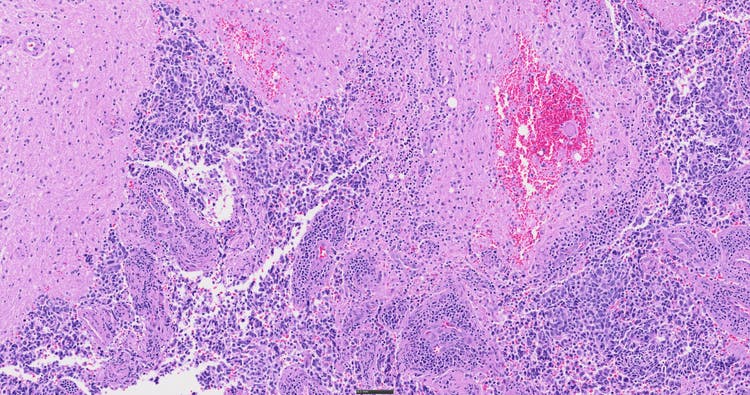

SLIDEVIEW DX VS200扫描仪可为各种病理学应用提供高分辨率、高通量的全玻片扫描,可适应多种玻片类型、放大倍率和成像模式。该系统旨在通过卓越的图像质量、可靠性和易用性来支持临床工作流程。